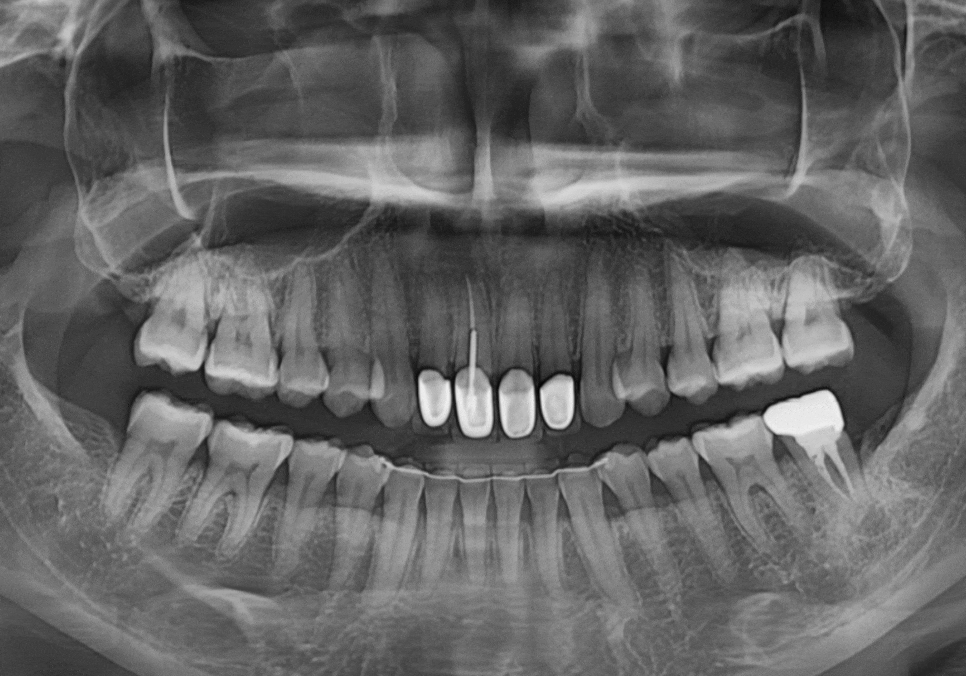

하지만 엑스레이 사진을 찍어보니

치아 뿌리 끝부분에

까맣게 나타나는 영역이 보이시나요?

250508

뿌리 끝에 염증이 생겨 주위 뼈가 녹아내리면

방사선상에서 저렇게

까만 그림자처럼 나타납니다.

환자분이 느끼셨던 욱신거림은

잇몸 뼈 안에서 염증이 보내는 신호였던 것이죠.